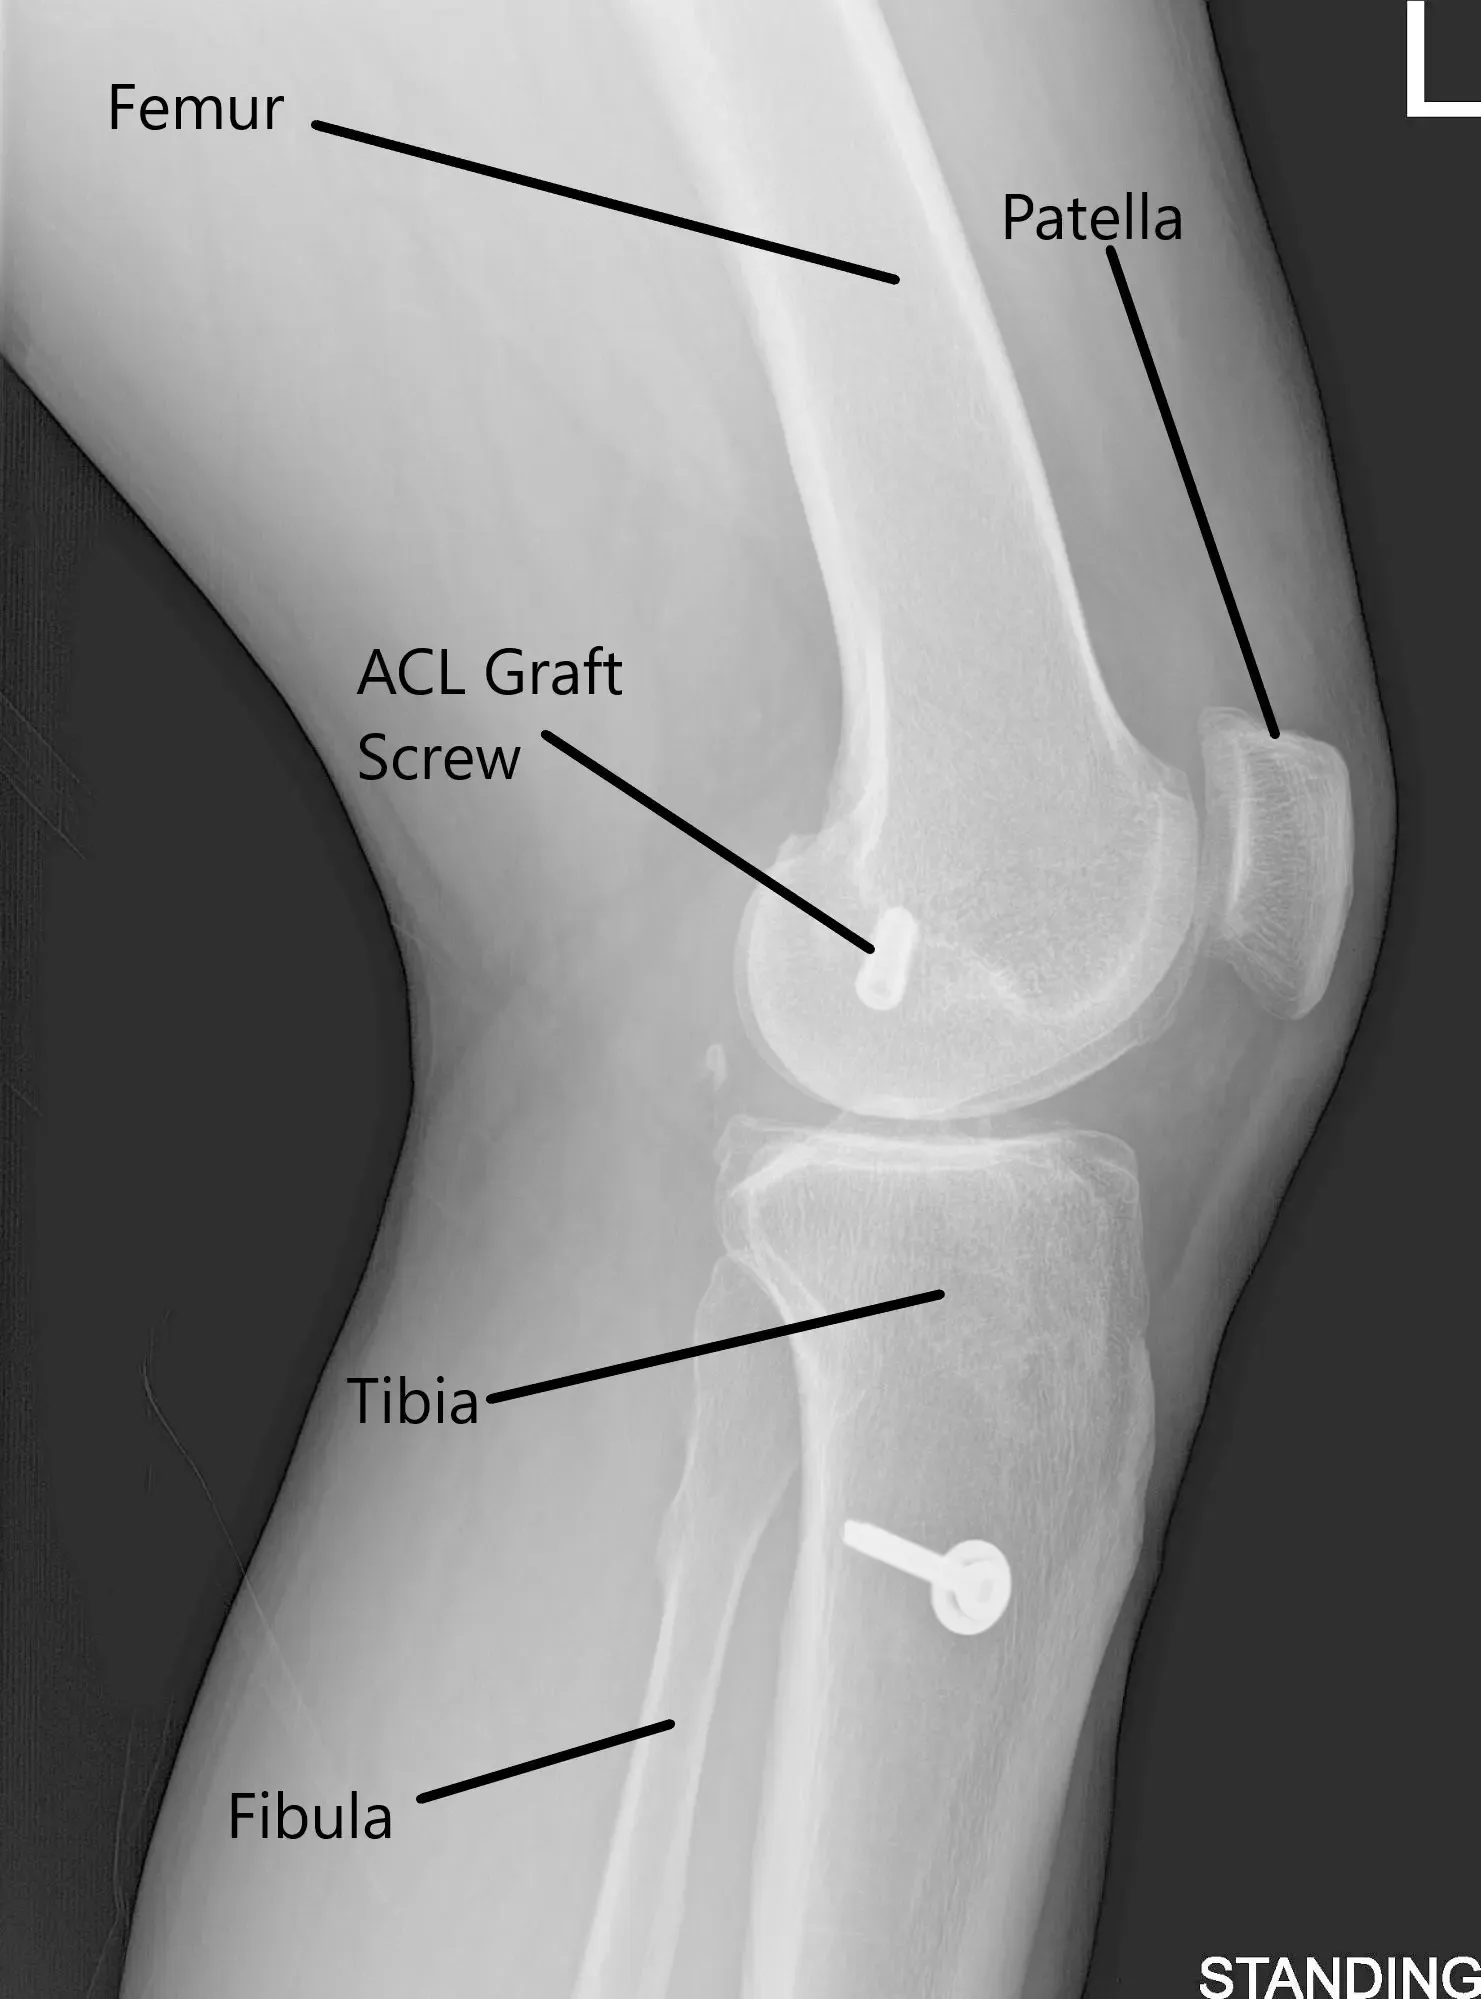

Radiografía de la rodilla izquierda en vistas AP y lateral.

Una radiografía de la quilla izquierda sugirió un estrechamiento moderado del compartimento articular medial y un estado tras la reconstrucción del LCA.